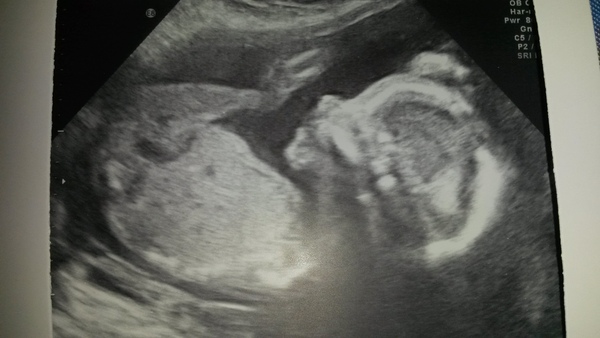

All was ok with the scan Smile We stayed team yellow and I'm surprised to find I have an anterior placenta given how much I have felt - it must be the wriggly nature of scooby!

Lovely to see the scan pics, there must be a few coming up over the next week or so? Mine is a week Thursday.